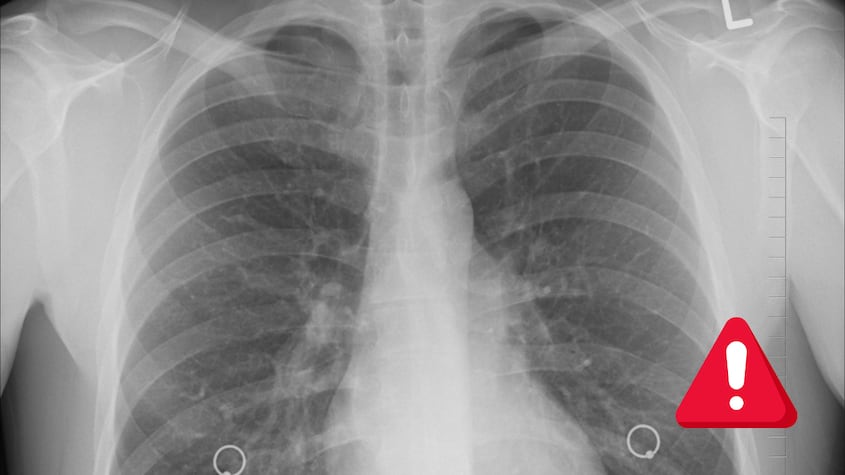

Cada 17 de noviembre, el mundo conmemora el Día Mundial de la Lucha contra el Cáncer de Pulmón, una fecha dedicada a aumentar la conciencia pública sobre esta enfermedad y sus devastadoras consecuencias, a la vez que promueve la prevención y el acceso a tratamientos adecuados. Esta jornada busca iluminar una problemática que representa una de las principales causas de muerte a nivel global, pero que, al mismo tiempo, es altamente prevenible.

El cáncer de pulmón es responsable de aproximadamente 1,8 millones de muertes cada año, lo que lo convierte en el tipo de cáncer más letal en el mundo, de acuerdo con datos de la Organización Mundial de la Salud (OMS). Este tipo de cáncer es más comúnmente causado por el tabaquismo, pero también afecta a personas que nunca han fumado. De hecho, factores como la exposición al humo de segunda mano, la contaminación del aire y ciertos agentes químicos también incrementan el riesgo de padecerlo.

El cáncer de pulmón se clasifica en dos tipos principales: el cáncer de pulmón de células no pequeñas (CPCNP), que representa aproximadamente el 85% de los casos, y el cáncer de pulmón de células pequeñas (CPCP), que es más agresivo y tiende a propagarse rápidamente. Aunque ambos tipos son peligrosos, el CPCNP suele tener mejores opciones de tratamiento y una tasa de supervivencia ligeramente más alta si se detecta en etapas tempranas.

El diagnóstico temprano es fundamental para mejorar las tasas de supervivencia. No obstante, la mayoría de los casos de cáncer de pulmón son diagnosticados en etapas avanzadas, cuando los síntomas se vuelven más evidentes, y el tratamiento es menos efectivo. Entre los síntomas iniciales se encuentran la tos persistente, el dolor en el pecho, la dificultad para respirar, la fatiga y la pérdida de peso sin razón aparente.

La detección temprana a través de estudios como la tomografía computarizada de baja dosis (LDCT, por sus siglas en inglés) ha demostrado ser efectiva para reducir la mortalidad en pacientes de alto riesgo, especialmente entre fumadores y exfumadores.